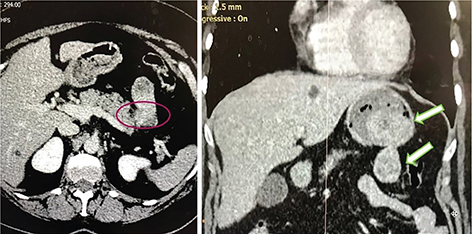

GISTs do not have specific endoscopic or endoscopic ultrasound (EUS) features, and often they are identified during endoscopy like a submucosal tumor (SMT), with pathological diagnosis only after surgery. In SMTs that are smaller than 2 cm with no high-risk features, and also in cases where histological diagnosis of GISTs was made after biopsy, only endoscopic follow up can be carried out until the patient becomes symptomatic or the tumor grows in size (24). The decision-making process may also include a histological diagnosis by EUS-guided fine-needle aspiration (EUS-FNA) biopsy. The optimal follow-up timing for these lesions is still debated in the literature, so an initial short-term follow-up at six months with EUS is recommended, which may then be deferred in time if high-risk features do not appear. This prolonged follow-up does not worsen the prognosis of patients with gastric GIST, as confirmed by a recent retrospective study (26). Endoscopic resection of SMTs is not considered oncologically safe, due to the risk of positive margins and high risk of cells dissemination. EUS-FNA biopsy can provide a histological diagnosis before surgery and set the indications for neoadjuvant therapy on the basis of the histological characteristics. EUS-FNA biopsy is to be preferred instead of conventional endoscopic forceps biopsy, because standard biopsy forceps do not reach the lesion beyond the normal mucosa and submucosa (27). However, EUS-FNA biopsy is not necessary for tumors measuring less than 2 cm, for undoubtedly benign tumors and for tumors which have already been planned for surgical resection (28). Instead, contrast enhanced computed tomography (CT) is recommended for initial diagnosis of tumors larger than 2 cm in diameter (Figure 1), to evaluate for the presence of high-risk features (25, 26). Furthermore, the Japanese guidelines recommend surgical resection for all GISTs that are larger than 5 cm in diameter (29). Finally, in metastatic disease, a biopsy of an easily accessible metastatic site can be performed, followed by a local and/or systemic treatment.

Fig 1

Figure 1. CT Scans. Abdominal CT scans showing an intraluminal and extraluminal gastric GIST. On the left, the extraluminal portion of the lesion is in close contact with the tail of the pancreas with no signs of infiltration. On the right, the two portions of the lesion, in continuity with each other, are shown by the arrows.